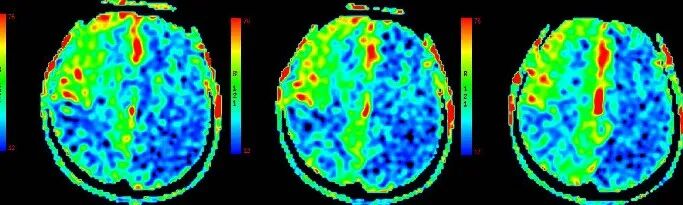

既往影像检查

导丝怎么扩【载药时代 球扩天下】NOVA DES®颅内药物洗脱支架在颅内富穿支区域使用体会二例!_https://www.jmylbn.com_新闻资讯_第3张

导丝怎么扩【载药时代 球扩天下】NOVA DES®颅内药物洗脱支架在颅内富穿支区域使用体会二例!_https://www.jmylbn.com_新闻资讯_第4张

导丝怎么扩【载药时代 球扩天下】NOVA DES®颅内药物洗脱支架在颅内富穿支区域使用体会二例!_https://www.jmylbn.com_新闻资讯_第5张

重要影像结论:3月前脑血管造影左侧大脑中动脉闭塞

导丝怎么扩【载药时代 球扩天下】NOVA DES®颅内药物洗脱支架在颅内富穿支区域使用体会二例!_https://www.jmylbn.com_新闻资讯_第8张

导丝怎么扩【载药时代 球扩天下】NOVA DES®颅内药物洗脱支架在颅内富穿支区域使用体会二例!_https://www.jmylbn.com_新闻资讯_第9张

ASL

重要影像结论:3月前ASL示:左侧额颞顶枕叶、右侧颞枕叶血流灌注量明显减低。